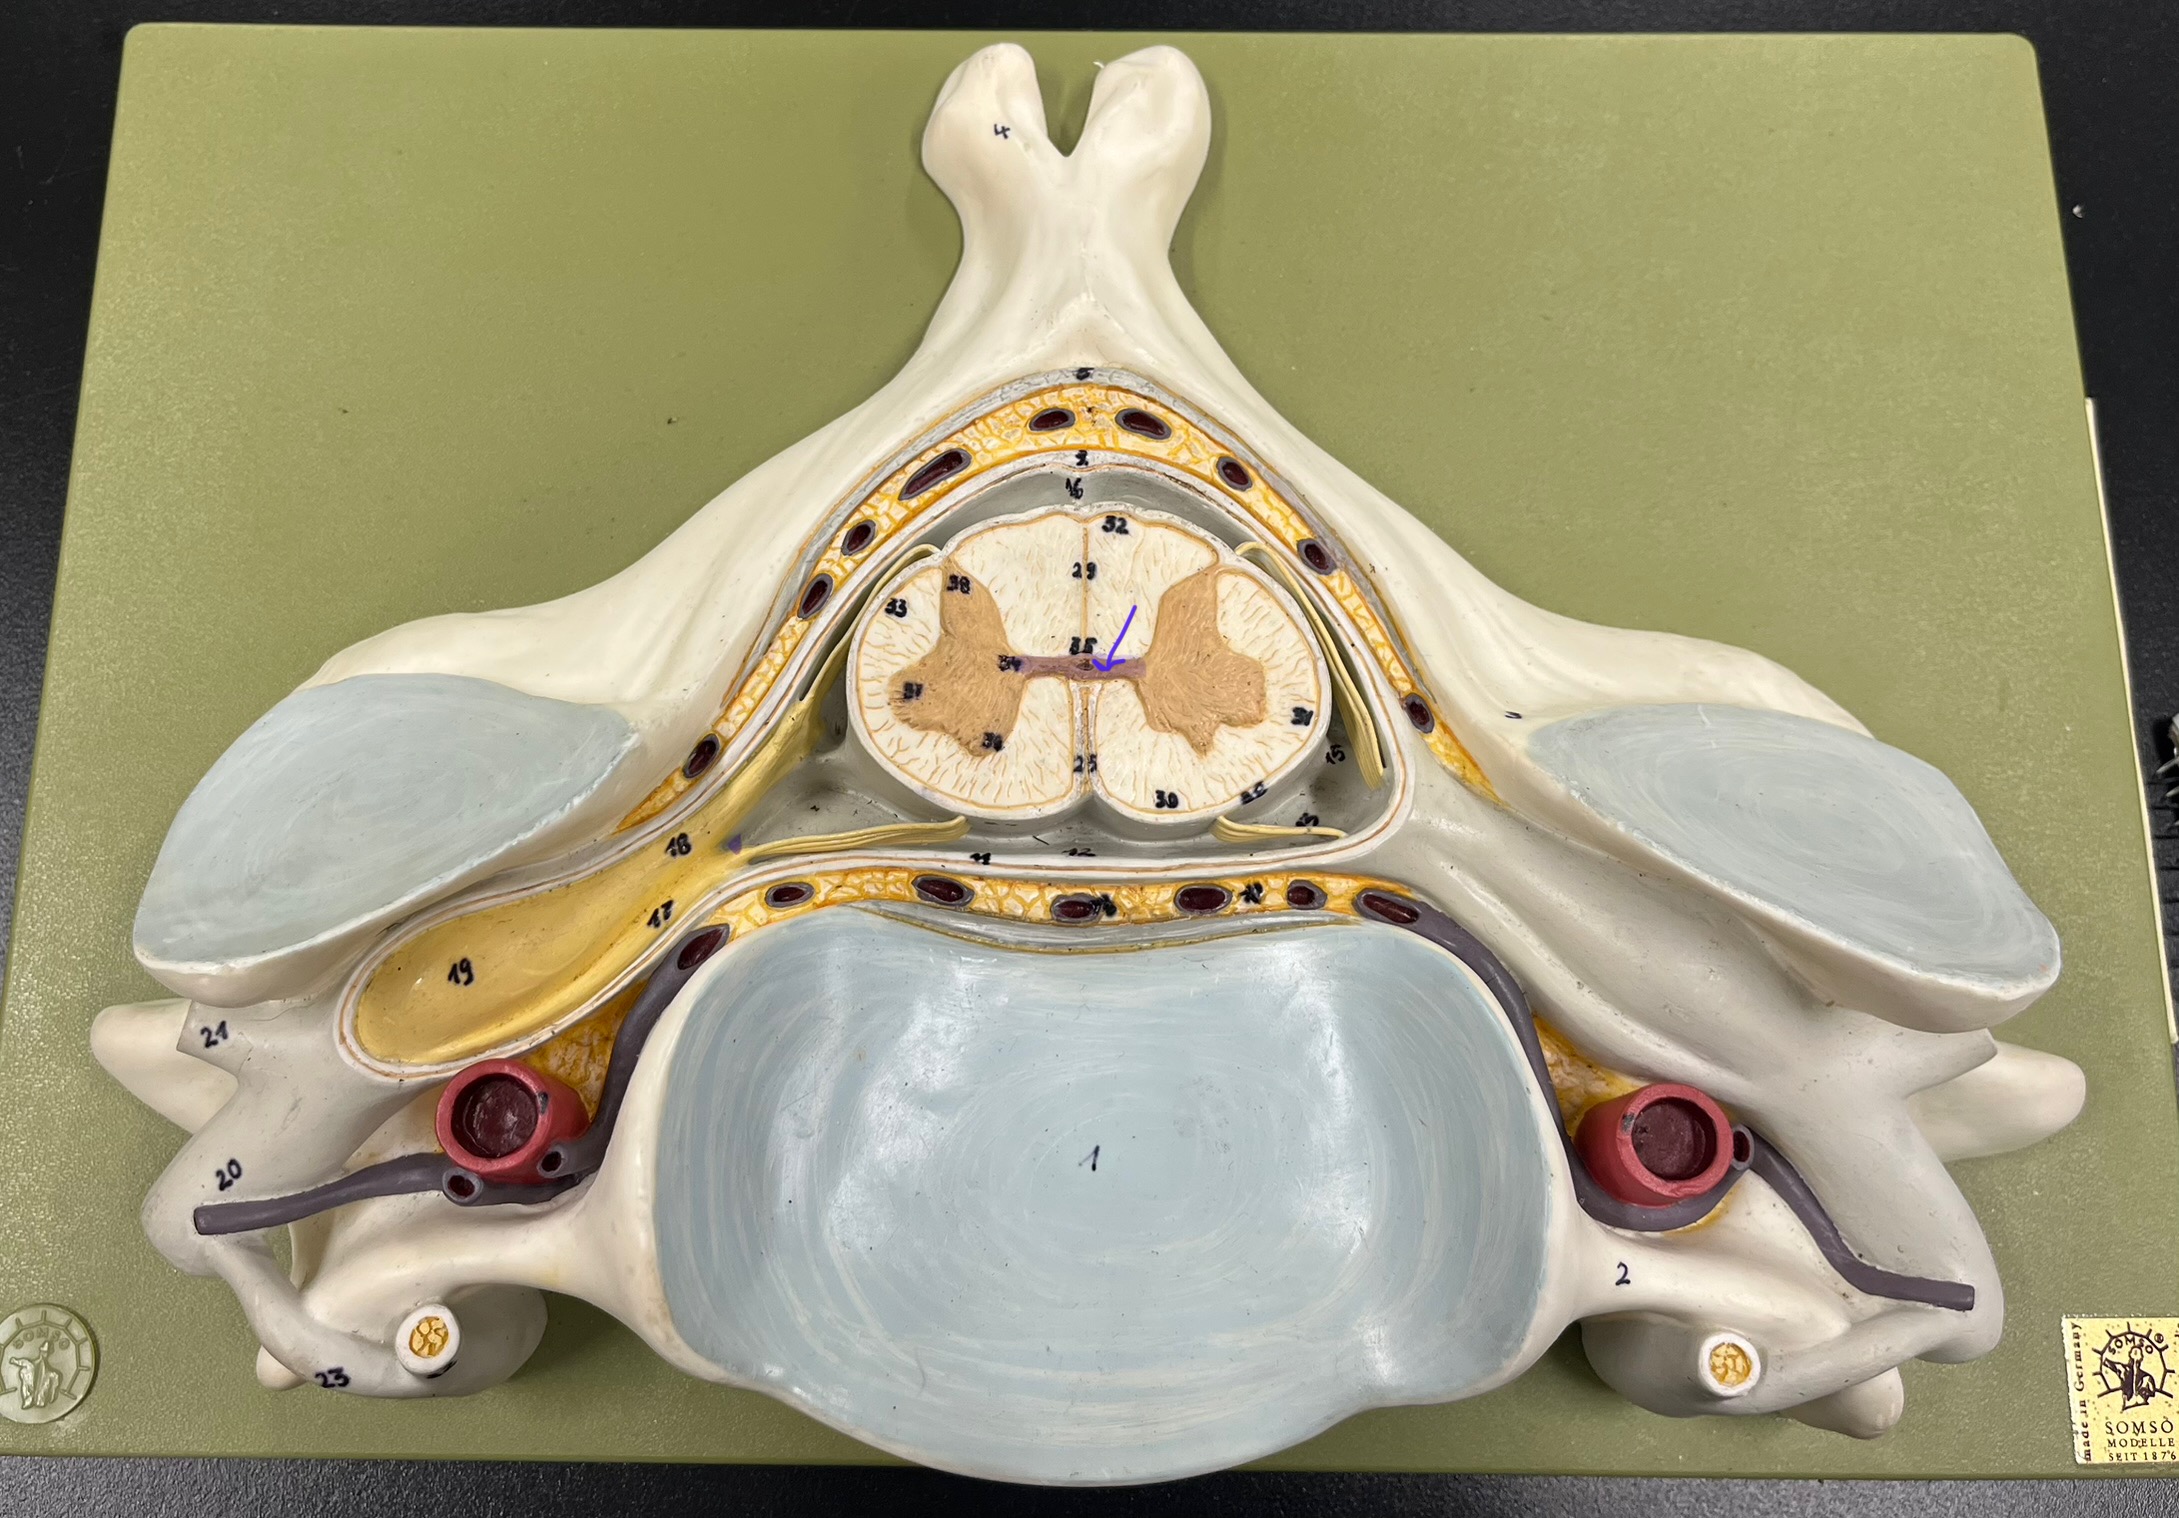

What is the groove here?

anterior median fissure

posterior median sulcus

posterior (dorsal) horn

posterior (dorsal) horn; R—>L

anterior (ventral) horn

lateral horn (selected models)

gray commissure

central canal

anterior column

lateral column

posterior column

white commissure

posterior (dorsal) root ganglion

What is the bulb here?

posterior (dorsal) root ganglion

posterior (dorsal) root

posterior (dorsal) root

anterior (ventral) root

anterior (ventral) root

dorsal ramus

dorsal ramus

ventral ramus

ventral ramus

rami communicantes

rami communicantes

sympathetic chain ganglia

sympathetic chain ganglia